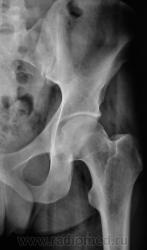

Пациент направлен на рентгенографию тазобедренного сустава с диагнозом ДОА.

Наряду с очагом в головке, видится мне ещё и перелом - линейное нарушение кортикального слоя. И ещё очаг в крыле подвздошной кости (но может и придираюсь). Я бы взял изначально на МРТ таза и тазобедренных суставов.

Тут умеренная грибовидная чуть шейка укорочена...М-ть укладка сдрейфила и носками наружу уложили? никаких деструкций не вижу А в подвздошной кости газики ну итрохантер хорош